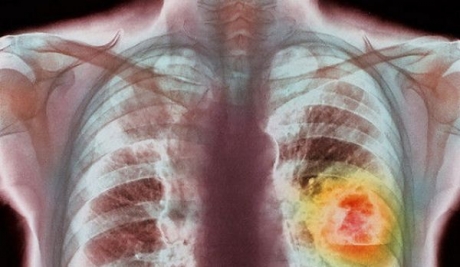

Persoanele care trÄiesc la o distanÅ£Ä de pânÄ la 50 de metri de drumurile cu trafic intens sunt expuse la creÅterea riscului de cancer pulmonar cu pânÄ 10%, conform unui raport publicat recent în Marea Britanie Åi citat de Press Association, anunÈÄ AGERPRES.

Studiul, efectuat de cercetÄtori de la King’s College London Åi lansat de o coaliÅ£ie alcÄtuitÄ din cincisprezece organizaÅ£ii nonguvernamentale care activeazÄ Ã®n domeniile sÄnÄtÄÅ£ii Åi mediului, demonstreazÄ cÄ proximitatea faÅ£Ä de drumurile aglomerate creÅte riscul de cancer pulmonar Åi poate sÄ afecteze dezvoltarea plÄmânilor copiilor cu pânÄ la 14%.

Realizat în 13 oraÅe diferite din Marea Britanie Åi Polonia, studiul sugereazÄ cÄ poluarea atmosfericÄ poate contribui la o creÅtere a riscului de boli de inimÄ, accident vascular cerebral, insuficienÅ£Ä cardiacÄ Åi bronÅitÄ.

Raportul a analizat treisprezece probleme de sÄnÄtate diferite prezente la persoanele care locuiesc în zone cu poluare atmosfericÄ ridicatÄ Åi le-a comparat cu restul populaÅ£iei, concentrându-se nu doar asupra internÄrilor în spitale Åi a deceselor, ci Åi asupra simptomelor, precum infecÅ£iile respiratorii.

Ãn cazul în care poluarea atmosfericÄ este redusÄ cu o cincime ar exista, spre exemplu, cu 3.865 mai puÅ£ine cazuri de copii cu simptome de bronÅitÄ Ã®n Londra, cu 328 în Birmingham, cu 94 în Bristol, cu 85 în Liverpool, cu 85 în Manchester, cu 134 în Nottingham, cu 38 în Oxford Åi cu 69 mai puÅ£ine în Southampton.

Studiul a concluzionat, de asemenea, cÄ poluarea atmosfericÄ din zonele limitrofe drumurilor cu circulaÅ£ie intensÄ a stopat dezvoltarea plÄmânilor la copii cu aproximativ 14% în Oxford, 13% în Londra, 8% în Birmingham, 5% în Liverpool, 3% în Nottingham Åi 4% în Southampton.